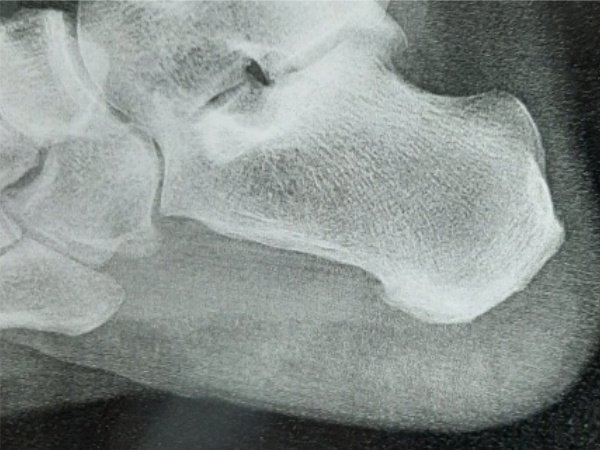

Raio-X mostrando esporão de calcâneo e diagnóstico profissional em Vila Velha ES

Imagem radiológica evidenciando esporão de calcâneo e sua localização no osso do calcanhar

O esporão de calcâneo é uma calcificação óssea que se forma na parte inferior do osso do calcanhar. Essa pequena saliência óssea geralmente se desenvolve devido à tração repetitiva da fáscia plantar e pode causar dor intensa ao caminhar ou ficar em pé.

Embora nem todo esporão cause dor, quando associado à fascite plantar (inflamação da fáscia que conecta o calcanhar aos dedos), pode gerar desconforto significativo, especialmente nos primeiros passos da manhã ou após longos períodos de repouso.